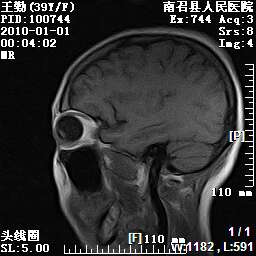

以下是引用随光逐影在2010-1-22 9:03:00的发言:[br]考虑左侧中颅窝(蝶骨翼区)脑膜瘤侵犯蝶骨翼并突入左侧眼眶。

以下是引用水过无痕在2010-1-22 14:55:00的发言:[br]一、定位:颅外占位;二、定性:恶性可能性大;三、组织来源:来源于左侧眼外直肌或其他部位;考虑为:横纹肌肉瘤>转移瘤>脑膜瘤.